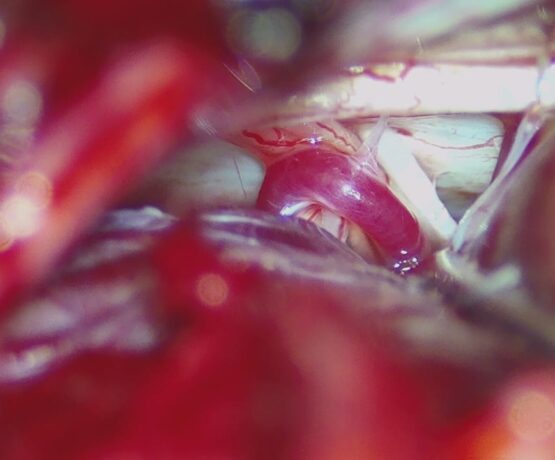

Lminectomy C3 down to C6 augmented by lateral mass fixation

Male 55 year daibetc known CSM operated 5 years by C5 C4 lamenectomy Pre operative Presented by progressive mylopathy VAS neck pain 8JOA score 9Preoperative…